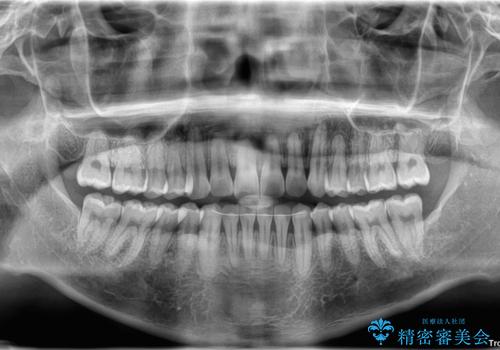

診察したところ、上下顎前歯部に軽度の叢生(ガタつき)が認められます。

目立たない装置を希望されたのでインビザライン ライトパッケージで治療を行うことになりました。